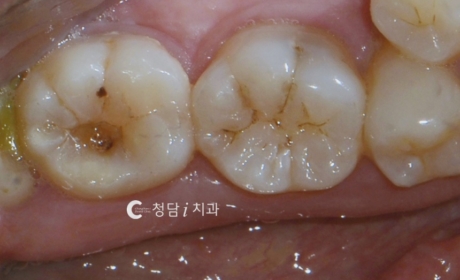

환자분의 경우 어금니 후방부가 부분적으로 파절되었으나, 신경 손상은 없어 보존적 치료가 가능했습니다. 손상 범위를 정확히 진단한 후, 치아 색상과 유사한 세라믹 인레이 치료를 진행했습니다.인레이는 파절 부위를 정밀하게 복원해주어 씹는 기능 회복은 물론, 금속이 보이지 않아 심미성 또한 우수합니다.